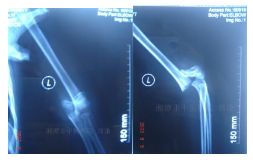

外院片如下:

入院后行四步复位法整复骨折,小夹板外固定,拍片复查